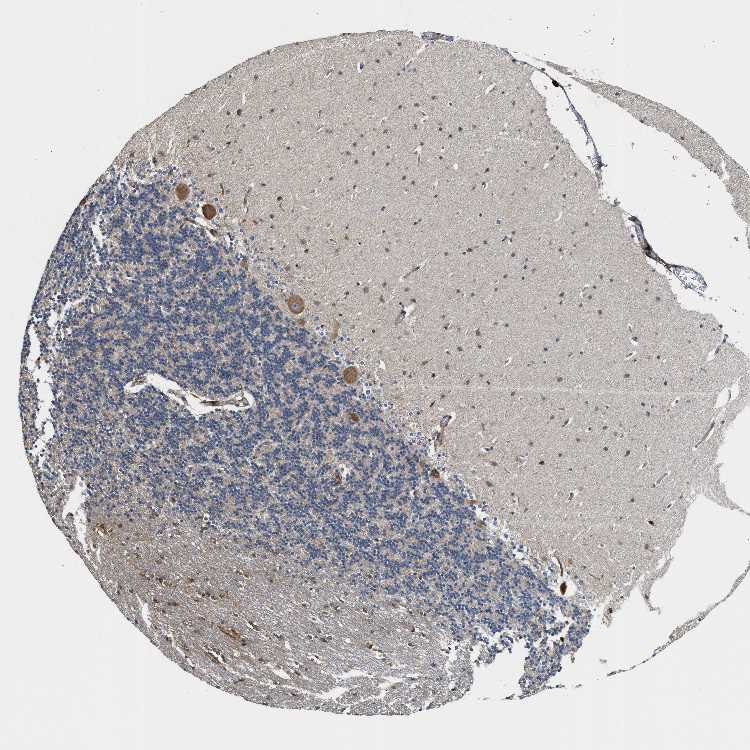

CEREBELLUM - Antibody stainingi

Antibody staining in the annotated cell types in the current human tissue is reported as not detected, low, medium, or high, based on conventional immunohistochemistry profiling in selected tissues. This score is based on the combination of the staining intensity and fraction of stained cells.

Each image is clickable and will lead to virtual microscopy that enables deeper exploration of all samples and also displays staining intensity scores, fraction scores and subcellular localization as well as patient and tissue information for each sample.

Antibody HPA020514

Purkinje cells High

Cells in granular layer Not detected

Cells in molecular layer Medium